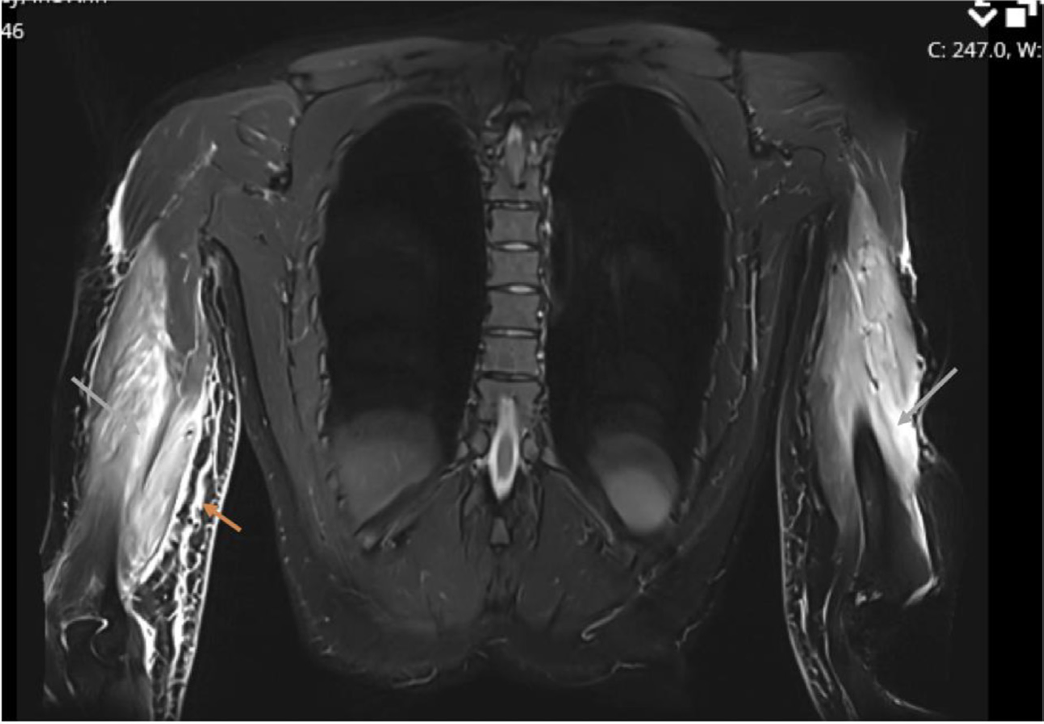

損傷した上腕三頭筋が白く写っています.

大腿の内側の筋肉(内転筋)が炎症を生じた結果, 白く写っています.

16時半過ぎにMRIが撮れたので, 確認しました. 腕にできた腫瘤の患者さんで, 腫瘍が疑われて紹介されてこられました. MRIでは, 明らかな腫瘍のような病変は認められず, 腕の筋肉(上腕三頭筋)が部分的に切れた状態(筋部分断裂:いわゆる肉離れ)と診断しました. ただし, 3年前に大学病院で甲状腺癌に対して甲状腺を切り取る手術が行われていました. 癌が筋肉の中に転移している状態も否定できません. 外来で経過を見て, 通常の筋部分断裂後の経過と異なる場合には, さらに検査を行うことを説明して, 次回の予約を入れました.